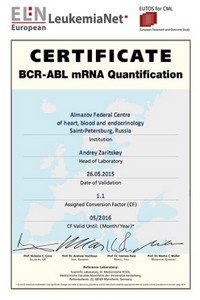

В 2011 году лаборатория молекулярной генетики ЦКДЛ совместно с НИЛ онкогематологии, выступая референс-лабораторией, первой в Российской Федерации завершила процесс стандартизации молекулярного метода количественного определения экспрессии гена BCR/ABL у больных хроническим миелолейкозом. Проведение данной работы осуществлялось совместно с European LeukemiaNet. Результаты этой работы в настоящее время позволяют осуществлять мониторинг минимальной остаточной болезни у данных пациентов, сопоставляя получаемые результаты с европейскими стандартами, а значит своевременно менять лечебную тактику.

Подтверждением успешного завершения данного процесса является получение международного сертификата.